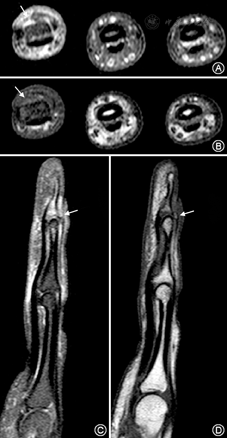

50例手指外伤患者中,侧韧带损伤患者33例,伸肌腱损伤10例,屈肌腱损伤4例。其中有8例在肌腱韧带损伤的同时伴有指骨或掌骨骨折。损伤的韧带及肌腱在T1WI序列表现为肌纤维增粗模糊、部分或完全不连续,PD-FS序列信号不均匀增高,纤维中断,其内可见水样高信号,损伤周围可见软组织水肿(图4,图5)。手指MR影像对比度和信噪比良好,屈伸肌腱和侧副韧带等主要结构显示清晰,可以满足影像诊断的需要。

手指肌腱和韧带在外伤后很容易发生损伤。因此,手外伤患者如要了解骨质情况以除外细微骨折等,应首选X线及CT检查,而临床上怀疑手指肌腱韧带损伤时首选MR检查。MR T1WI序列可清晰显示手指肌腱韧带的正常解剖结构及走行,在T1WI序列中,脂肪呈高信号,肌腱、韧带呈线样低信号,二者形成了良好的对比,更有利于显示正常解剖结构;而PD-FS序列对明确损伤部位、损伤程度及水肿、积液等病变结构更加敏感,更容易发现病变。

通常采用冠状位观察侧韧带的走行,轴位主要观察肌腱形态和覆盖于肌腱上相邻的支持带,以及是否有纵向撕裂或腱鞘积液[5] 。在临床上,最常见的手指侧韧带损伤为拇指掌指关节尺侧副韧带(UCL)损伤,MRI可以精确的根据有无内收肌腱膜的损伤将UCL损伤分为Stener损伤和非Stener损伤两型[6]。当发生伸肌腱和屈肌腱损伤时,通常采用矢状位和轴位观察。MRI可清楚显示矢状束、中央束、末端腱等手指伸肌结构以及伸肌腱和屈肌腱的损伤情况,尤其在急性期临床表现不典型时,矢状面为最佳检测平面[7]。文献报道,利用MRI图像与尸体解剖标本的对照,证实MRI对于伸、屈肌腱撕裂的诊断敏感性为92%,特异性为100%[8]。